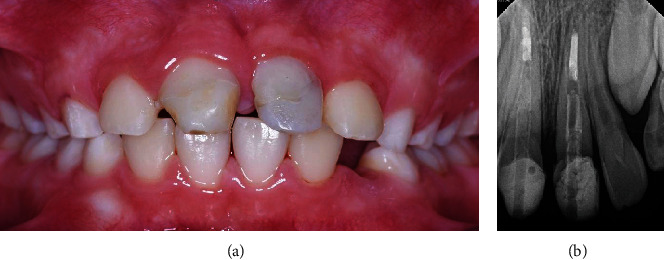

A few months later, the patient returned to the clinic free of any signs or symptoms. The teeth had normal mobility, normal percussion, and normal pocket depths. Given the positive findings, the patient was scheduled to complete his treatment. Teeth #11 and #21 were restored with temporary crowns (Protemp™ Plus, 3M, US), and both the patient and his parents were satisfied (Figure 11).

Figure 11.

(a) Clinical picture and (b) PA radiograph showing teeth #11 and #21 after temporary crown cementation.

The patient was given an appointment 2 weeks from the temporary placement for the completion of his final ceramic crowns. Unfortunately, this is the time that the country went into lockdown for COVID. The school closed, and all clinics were canceled. This made any follow-up impossible, and we were only able to see the patient approximately one year later, which was 30 months after starting the treatment. At this visit, a complete clinical and radiographic examination was performed and revealed that both central incisors were asymptomatic, there was no pain on percussion or palpation, and the teeth had normal pocket depths. The temporary crown for tooth #21 was missing. Periapical radiographs revealed a periapical radiolucency related to tooth #11 and revealed apical closure of tooth #21. A limited field CBCT confirmed the findings of a periapical lesion about 6 × 3 mm in size related to tooth #11 (Figure 12).

Figure 12.

(a) Periapical and (b) CBCT radiographs showing periapical lesion related to tooth #11 and apical closure of tooth #21.